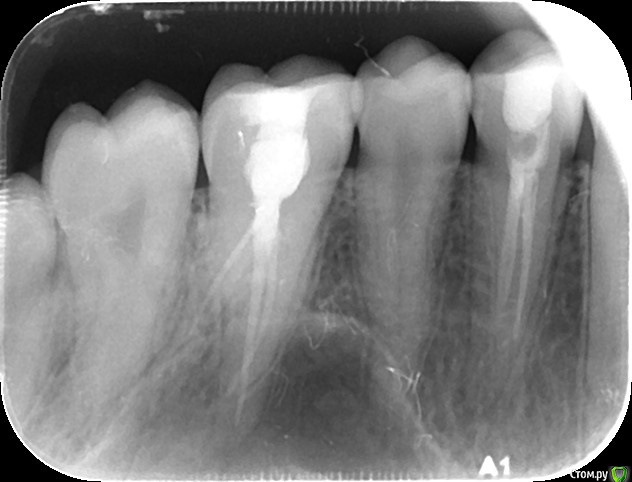

Nitrino1 Опубликовано 26 августа, 2016 Поделиться Опубликовано 26 августа, 2016 Уважаемые коллеги прошу у вас помощи так как сам не смог разобраться с данным случаем. Значит ситуация такая, приходила ко мне пациентка 3 месяца назад. Жалобы на боль слева сверху. Конкретно не знает какой зуб. Из анамнеза, боль появилась приблизительно год назад. Пошла к одному стоматологу, тот депульпировал 24-й заявляя что причина в нём. Боль не прошла. Пошли к другому стоматологу, тот заподозрил 26, депульпировал его. Боль не прошла. Пошли к третьему стоматологу, тот сказал что 24-й не правильно вылечен и "перелечил". Боль не прошла. Я четвёртый к кому они обращаются.Что имеем объективно. Пломбы на контактных пунктах нет. Десна была немного изменена в цвете в области сосочков между 24-25-26. При нажатии на десну небольшая боль. Перкуссия болезненная 24 и 26. Положил анестетик на десну - боль прошла. Заподозрил гингивит. Назначил лечение, флос, правильную чистку щеткой, Метрогил Дента на десну, Полоскание хлоргекседином и витамин общий. Боль прошла. Через неделю появилась, сделал в 3 посещения пасту из антибиотика и витамина А. Боль прошла на 2 месяца. Пришли ко мне недели 3 назад, те же самые боли. Перкуссия болезненна была на 24 в первое посещение. Во второе посещение болезенны были и 24 и 26. Промыл под сосочками хлоргексидином, назначил опять Метрогил Дента, полоскание хлоргекседином, правильную чистку. Прошла неделя, боли продолжаются. Помогите советами, что я упустил? Панораму сделал, там ничего такого. 24 и 26 вылечены не качественно и сам вижу, 24 даже в большей степени, но лечение десен же помогло, значит проблема в десне, а причину не могу определить. Ссылка на комментарий

сирена Опубликовано 26 августа, 2016 Поделиться Опубликовано 26 августа, 2016 На обоих зубах очаги,чё тут думать?Мазилки помогли не благодаря,а вопреки.Может,рефлекторное воздействие или самовнушение.Я так полагаю. 1 Ссылка на комментарий

DmitrySH Опубликовано 26 августа, 2016 Поделиться Опубликовано 26 августа, 2016 На обоих зубах очаги,чё тут думать?Мазилки помогли не благодаря,а вопреки.Может,рефлекторное воздействие или самовнушение.Я так полагаю. Поддерживаю. Если трудности с диагностикой, то лучше начать с очевидных вещей. В данном случае ревизия каналов точно нужна. Ссылка на комментарий

Nitrino1 Опубликовано 27 августа, 2016 Автор Поделиться Опубликовано 27 августа, 2016 Коллеги я с Вами согласен, сам так же хотел с перелечки начать, но напрягает два факта: боли начались до того как ей депульпировали два этих зуба и второй фактор - переходная складка не болезненная + после лечения десен 2 месяца болей не было + ей антибиотики назаначали перорально, а они как известно купируют хронический периодонтит, так вот, они ей вообще не помогли. Думаете все равно причина в 24 и 26? 28-ой я посмотрел сразу же, он прорезался но не полностью, в той области пальпация безболезненна, перкусия 27 тоже безболезненна. На 28 очагов кариеса нет Ссылка на комментарий